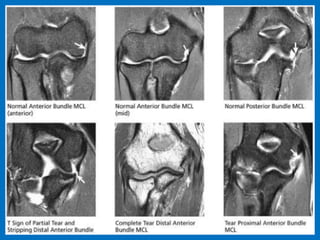

Ulnar collateral ligament (UCL) injury refers

to a sprain, partial tear or complete tear of

the ligament that traverses the inside (or

medial side) of the elbow. The UCL is the

primary stabilizer of the elbow and plays an

important role in throwing and hitting

sports, such as baseball, football and tennis.

Additional findings: Strain or rupture of the

common flexor tendon, ulnar neuropathy,

ulnar traction spurring or heterotopic

ossification of the soft tissues

and medial flexor insertion pronator tear.